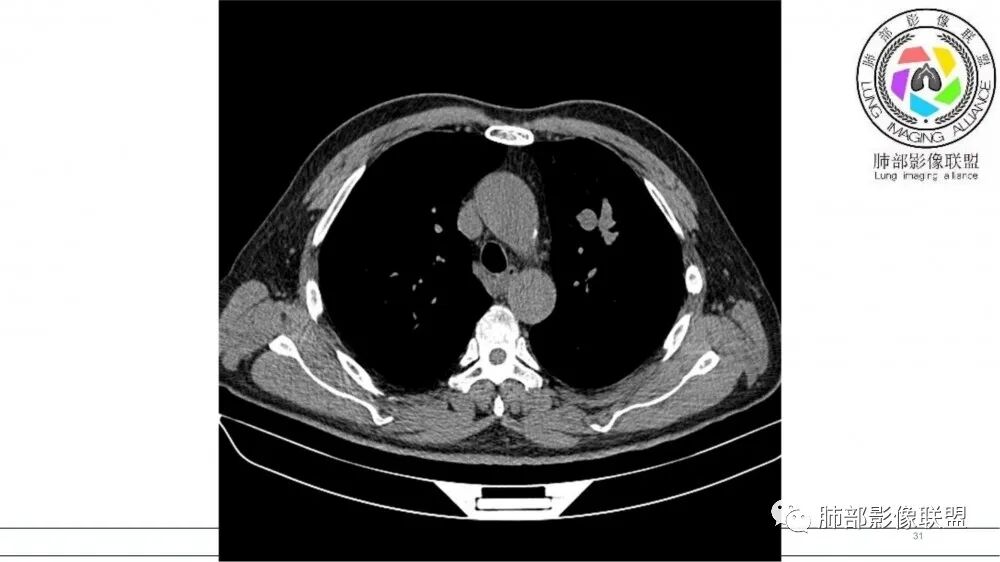

猜个鳞,沿支气管塑型生长,周围小花小草,肺门及纵隔淋巴结增大,吸烟老年男。鉴别TB

左肺上叶前段支气管内铸形生长软组织影,增强后均匀强化,远侧见斑片状磨玻璃影。考虑恶性病变,粘表?粘液腺?

考虑恶性占位,沿支气管塑型生长,增强未见明显强化,首先考虑鳞癌,鉴别APBA及结核,感觉不像,最后挂上小细胞肺癌。

老年男性,左肺上叶前段支气管内铸形阴影,增强后病灶不均匀强化,内部有坏死?远端可见斑片状阴影(阻塞性肺炎)。考虑恶性病变,老年人,鳞?类癌?粘表不能排除。

左肺上叶前段支气管杵状指样扩张,内见实性组织阻塞性,并强化明显,边缘饱满,周边多发小斑点影,小花小草征,老年男性,长期吸烟史,方向恶性,首选支气管内浸润鳞Ca可能性大。

男,70岁,吸烟史,咳嗽,胸闷憋气一个月,左肺上叶不规则形软组织密度影,病灶沿支气管走形,周围见粟粒及棉絮样稍高密度影,增强扫描病灶内见少许坏死,考虑鳞癌可能,鉴别结核。

老年男性,肺气肿,吸烟史,左肺上支气管腔内铸型高密度影,呈指套状,远端多发树芽,增强不均匀强化,考虑鳞癌,鉴别小细胞癌

B3指套征,常规不是鳞癌就是ABPA,有强化丶血管造影征,倾向于鳞癌

老年男性,长期吸烟史。左上肺前段沿支气管走形的指套样病变,增强可见病灶强化(排除结核、ABPA(也无气喘症状)),远端多发点状高密度影。考虑恶性肿瘤,鳞癌可能性大。

指套征,扩张支气管内软组织强化,远侧肺野阻塞性炎,纵隔、左肺门肿大淋巴结;老年男性,吸烟,考虑鳞癌,鉴别小

老年男性,术前检查肺气肿背景,左肺上叶结节,沿支气管蠕虫样生长,左肺门及纵隔淋巴结肿大,增强扫描不均匀强化,血管包绕,结合吸烟史,考虑小细胞肺癌。

老年吸烟男性,尖前段支气管内塑形生长,增粗蠕虫样,没有肺不张(排除鳞癌?),远端少许阻塞肺炎,增强低强化,锁定小

老年男性,吸烟,指套征,蠕虫征,阻塞性炎症不严重。可见血管穿行,密度均匀,轻度强化,首先考虑小细胞肺癌。鉴别鳞

2021年8月6日晨读病例结果:小细胞肺癌